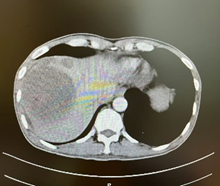

新辅助(两次HAIC和两个周期靶免治疗)后CT

由于病人一般情况较好,肝功能良好(Child-pugh A级),经多学科会诊临床确认肿瘤为IIb期肝细胞癌,属于可切除性肝癌,但存在高危复发因素,建议先行新辅助治疗后手术切除。经两次肝动脉关注化疗(HAIC)(奥沙利铂+5-Fu+亚叶酸钙方案)和两个周期的靶向免疫治疗(仑伐替尼+帕博利珠单抗方案),第二次介入造影是肿瘤血供不明显,第二次介入治疗4周后复查CT提示肿瘤缩小不明显但坏死征象明显,经MRI证实仍有少许血供,于是经多学科会诊后决定行前入路右半肝切除术。